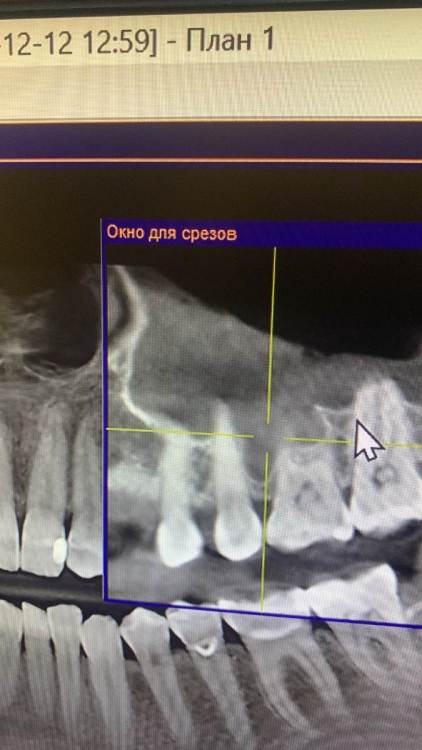

KOCTb Опубликовано 1 января, 2024 Поделиться Опубликовано 1 января, 2024 Здравствуйте коллеги. Может кто-то подскажет полезного. Пациентка. Лет 6 назад пришла с симптоматикой пульпита во втором секторе. На некоторых зубах были пломбы, без криминала. Зубы были проверены на витальность. Все живые. Пальпаторно передняя стенка ВП давала лёгкую чувствительность. Сделали КТ. Апикальных изменений не выявлено, а в пазухе слева признаки гайморита. Заполнена была бальше чем наполовину. Отправил к ЛОРу. Пролечили. Анатомическое строение не очень понравилось. С тех пор каждую зиму у неё обострение ВЧ синусита слева. Иногда даже два раза бывает. Каждый раз ЛОР в направляет к стоматологу и говорит, что гайморит одонтогенгый. Врачи рентгенологи в описании иногда там находят одонтогенгую кисту… Года два назад пациентка сходила поменяла все пломбы, на всякий пожарный. Со слов зубы все были витальные при лечении. Ну и собсвенно опять ВЧ синусит. Смущает анатомическое строение между 25 и 26 зубом. Не может ли там через периодонтальную щель «сифонить» ? Говорит между зубами иногда какой-то дополнительный дискомфорт есть. Ссылка на комментарий

KOCTb Опубликовано 3 января, 2024 Автор Поделиться Опубликовано 3 января, 2024 1 час назад, stommm сказал: 1. есть Кт где видно соустье в обострение? Есть ЛОР КТ. Не смотрел. (На руках не было). Думаете на анатомическую особенность в области 25-26 смысла нет упор делать ? Ссылка на комментарий

KOCTb Опубликовано 15 января, 2024 Автор Поделиться Опубликовано 15 января, 2024 19 часов назад, Astronaft сказал: Здравствуйте. 6 лет назад: подробнее про симптомы пульпита? как полечили гайморит и чего добились? Анатомия действительно интересная. Интуитивно, или естественная впадина которая способствует застою либо проблемы в соустье вызывают застой и кислотный секрет лизирует самое слабое место. Опять же интуитивно, пациентке приказать зубы не трогать, не ходить выискивать проблемы. Очень подробно расспросить анамнез, в том числе что помогает, что запускает синусит. Если соустье открыто то я бы рекомендовал регулярно промывать физраствором с ЭДТА и выждать. Здравствуйте. Ну как обычно пульпитная симптоматика при ВЧ синусите. Разлитые периодические боли в верхнем секторе, с непонятной локализацией. Пальпаторно передняя стенка ВЧ пазухи давала болезненность. От 25 до 27 зуба. На КТ зубов затенение в ВЧ пазухе. Отправил тогда к ЛОРу. Подробности лечения у ЛОР врача тогда не знаю. Синуситы в холодное время года. Соустье пародонтальным зондом не выявлено. Носо-ротовая проба также отрицательная. Но тут и понятно если и есть ход, то крайне мизерный. Там слизистой завалено всё. Ссылка на комментарий